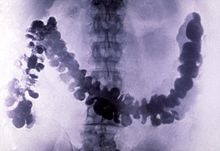

Barium has only a few industrial applications. The metal has been historically used to scavenge air in vacuum tubes. It is a component of YBCO ( high-temperature superconductors) and electroceramics, and is added to steel and cast iron to reduce the size of carbon grains within the microstructure of the metal. Barium compounds are added to fireworks to impart a green colour. Barium sulfate is used as an insoluble heavy additive to oil well drilling fluid, and in purer form, as X-ray radiocontrast agents for imaging the human gastrointestinal tract. Soluble barium compounds are poisonous due to release of the soluble barium ion, and therefore have been used as rodenticides.

In 1908, barium sulfate was first applied as a radiocontrast agent in X-ray imaging of the digestive system.

Barium sulfate has a low toxicity and relatively high density of ca. 4.5 g·cm−3 (and thus opacity to X-rays). For this reason it is used as a radiocontrast agent in X-ray imaging of the digestive system (" barium meals" and " barium enemas"). Lithopone, a pigment that contains barium sulfate and zinc sulfide, is a permanent white that has good covering power, and does not darken when exposed to sulfides.